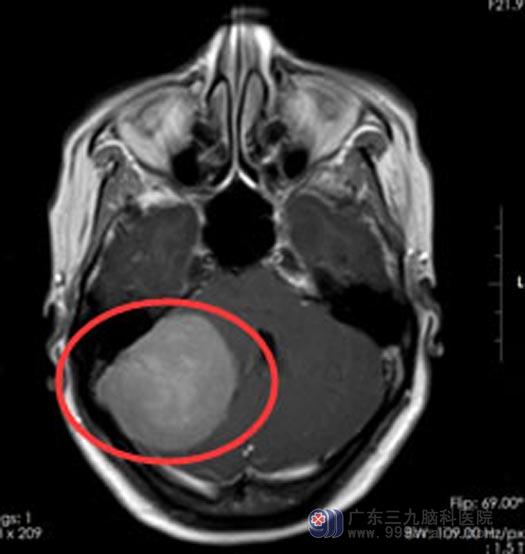

广东三九脑科医院头颅MR检查结果提示:右侧桥小脑角区一类圆形占位性病变,大小约37cm×52cm×47cm ,诊断为:右侧桥小脑角占位,考虑为脑膜瘤。

充分的检查与术前准备后,由综合神经外科鲁明副院长主刀在全麻下行“右侧桥小脑角占位切除术”。由于肿瘤体积巨大,手术难度极大,经过显微镜下几个小时的细心操作,肿瘤被完整切除。